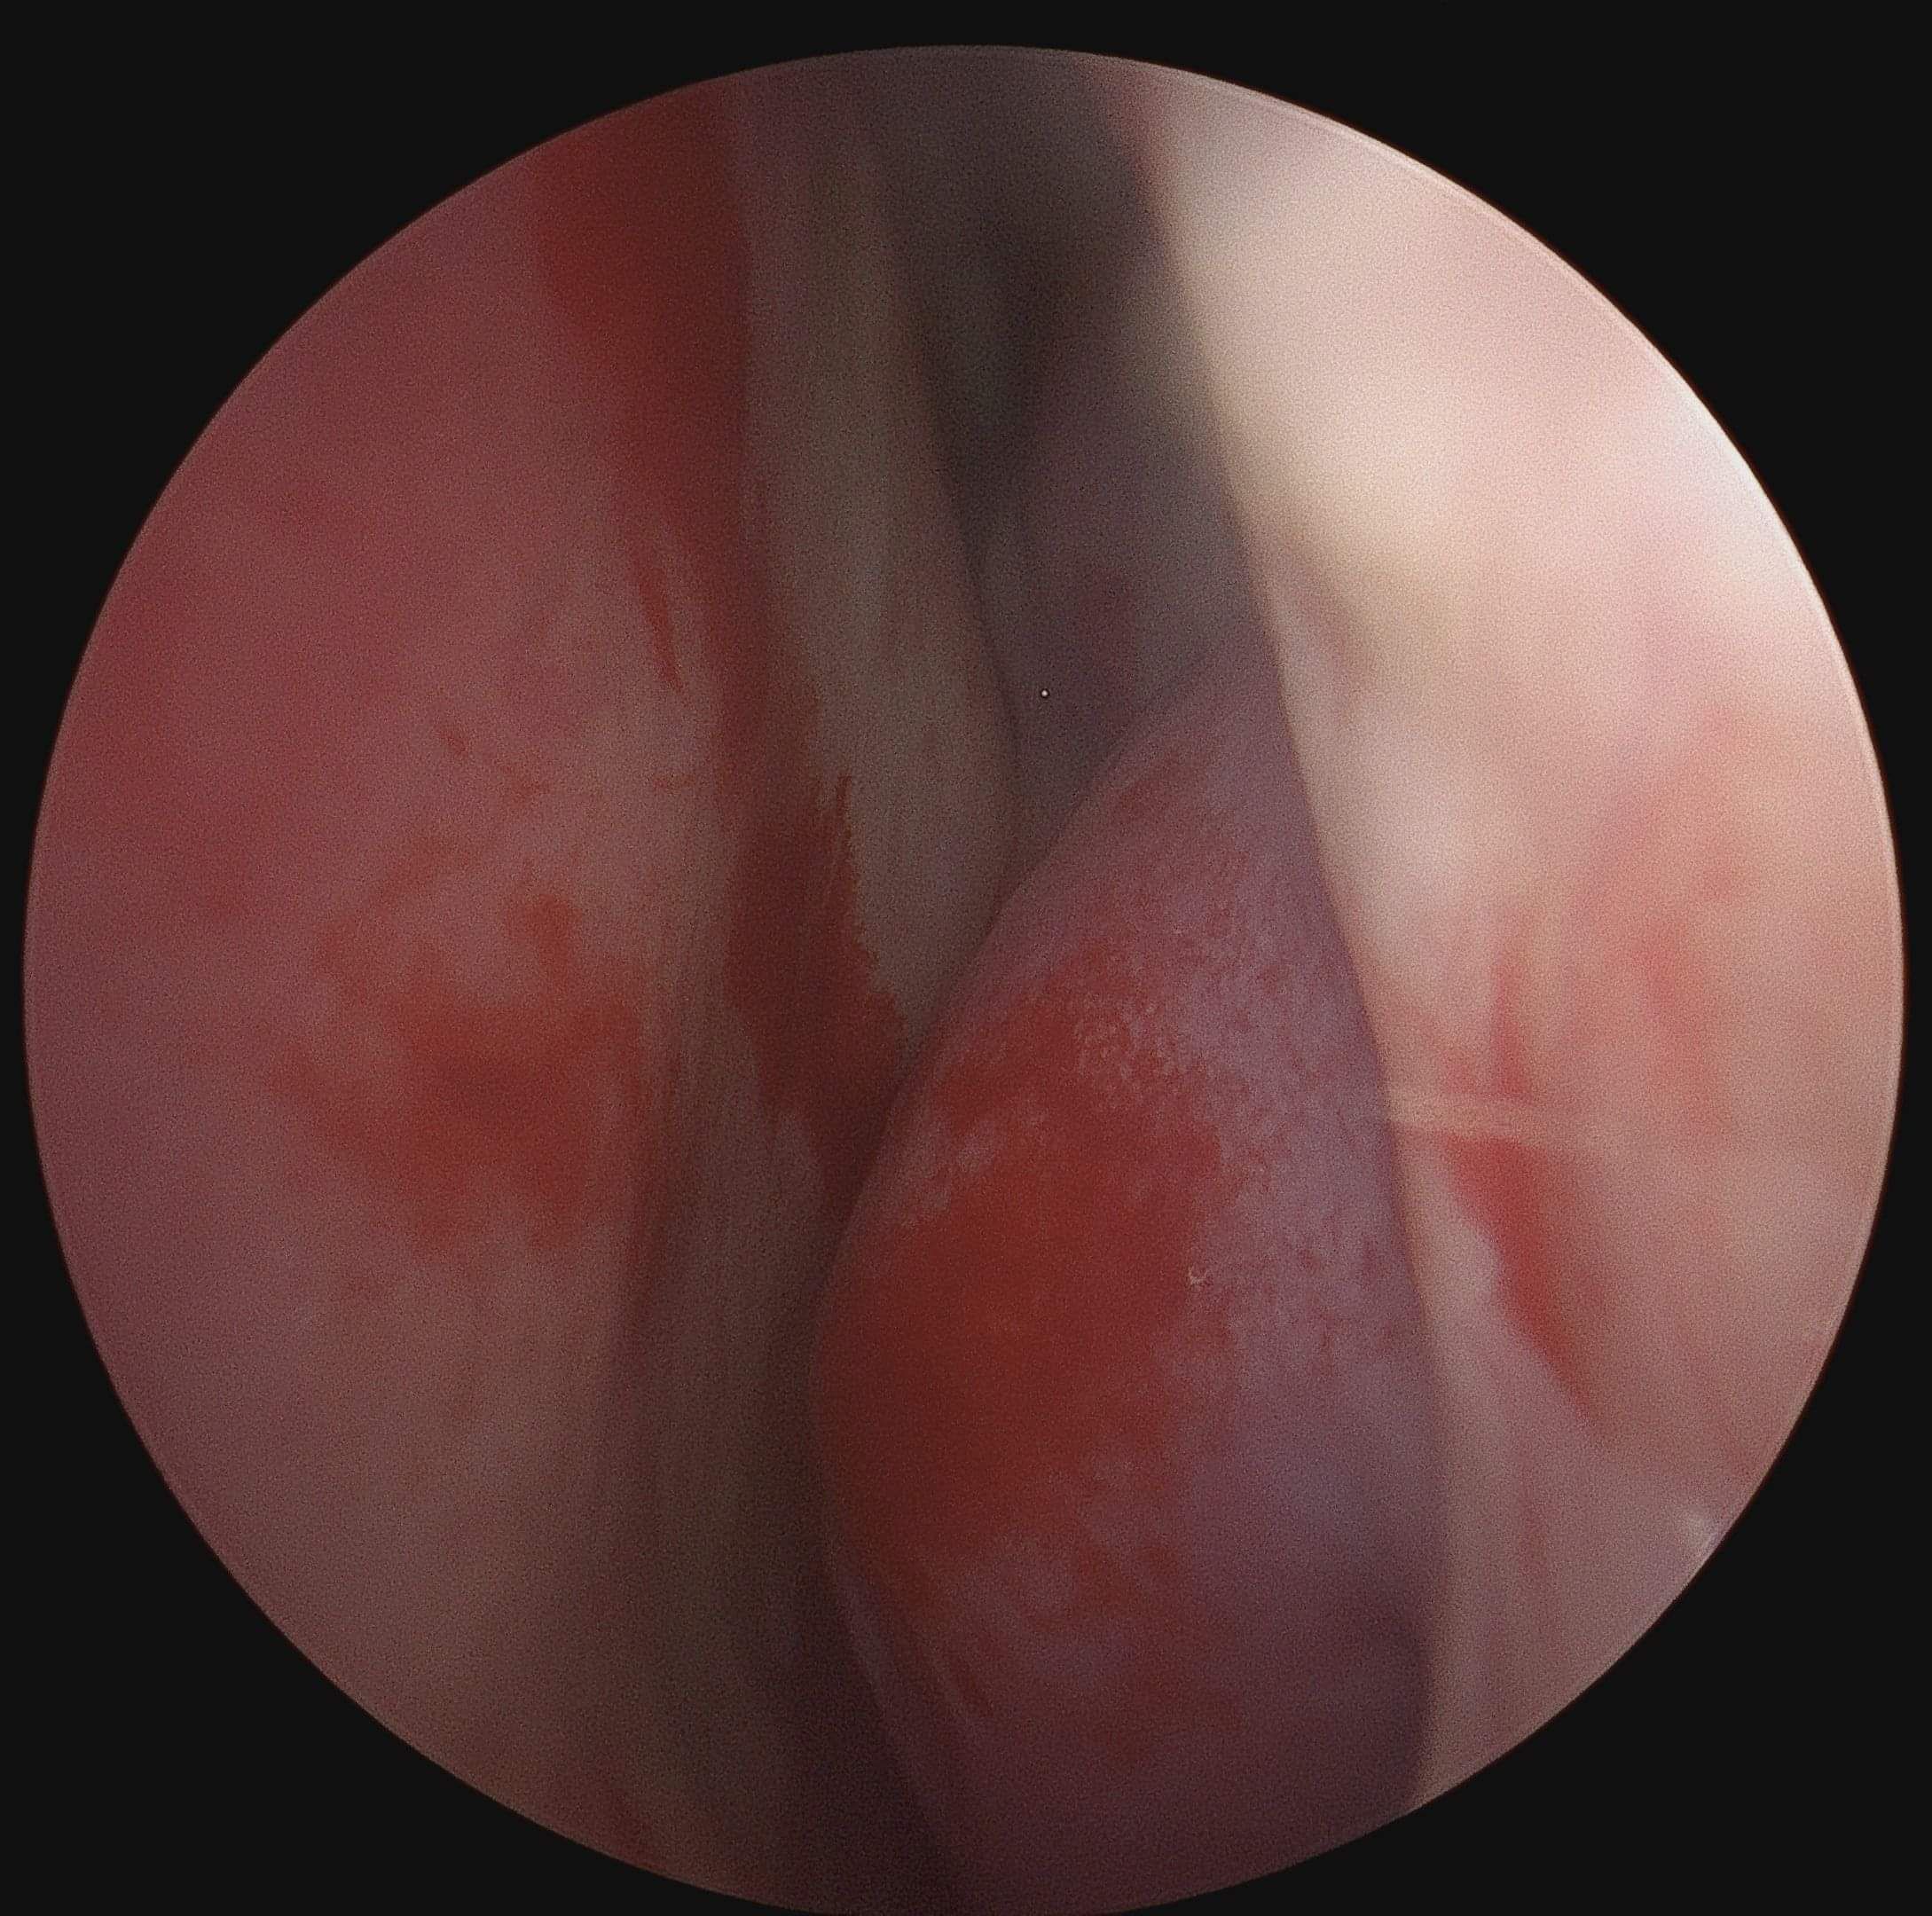

Turbinoplasty is a key-hole surgical procedure aimed at reducing the size or reshaping the nasal turbinates to improve nasal airflow and alleviate symptoms such as nasal congestion. It is typically considered for individuals who have chronic nasal obstruction that does not respond adequately to conservative treatments such as nasal sprays or medications. Common indications include: Inferior turbinate hypertrophy (enlargement), nasal valve collapse and chronic sinusitis.

For most patients, a procedure known as submucous resection (also called inferior turbinate reduction surgery, submucosal turbinoplasty or inferior turbinoplasty) can be used to treat the condition. This involves carefully lifting the mucosa (lining) covering the turbinate and dissecting it to expose the underlying turbinate bone. Using specialised instruments, the surgeon removes a portion of the horizontal component of the turbinate bone. This reduction in bone size helps to decrease the overall volume of the turbinate. Careful attention is paid to preserve as much of the mucosal lining as possible. The remaining mucosa is often reshaped and repositioned to maintain its function in humidifying and filtering the air passing through the nose.

The ARIS COBLATION Turbinate Reduction Wand is engineered to offer versatility in treating hypertrophic turbinates submucosally, providing surgeons with precise control over tissue removal tailored to each patient's needs. Utilising Smith+Nephew’s advanced COBLATION Plasma Technology, this wand ensures a minimally invasive approach for turbinate reduction procedures, emphasising customisation, flexibility, and surgical precision. This wand utilises Smith+Nephew’s advanced COBLATION Plasma Technology to provide a minimally invasive way to reduce hypertrophic turbinates. With three ablation and coagulation modes for desired tissue effect, it also provides intraoperative visual reduction of the turbinate and integrated haemostasis (process to prevent bleeding) with coagulation functionality.

The surgery is done endoscopically under general anaesthetic. There are no external scars and no facial bruising. The patient satisfaction rate is very high with this procedure and most patients report a significant improvement in breathing, sleep quality and their overall quality of life.